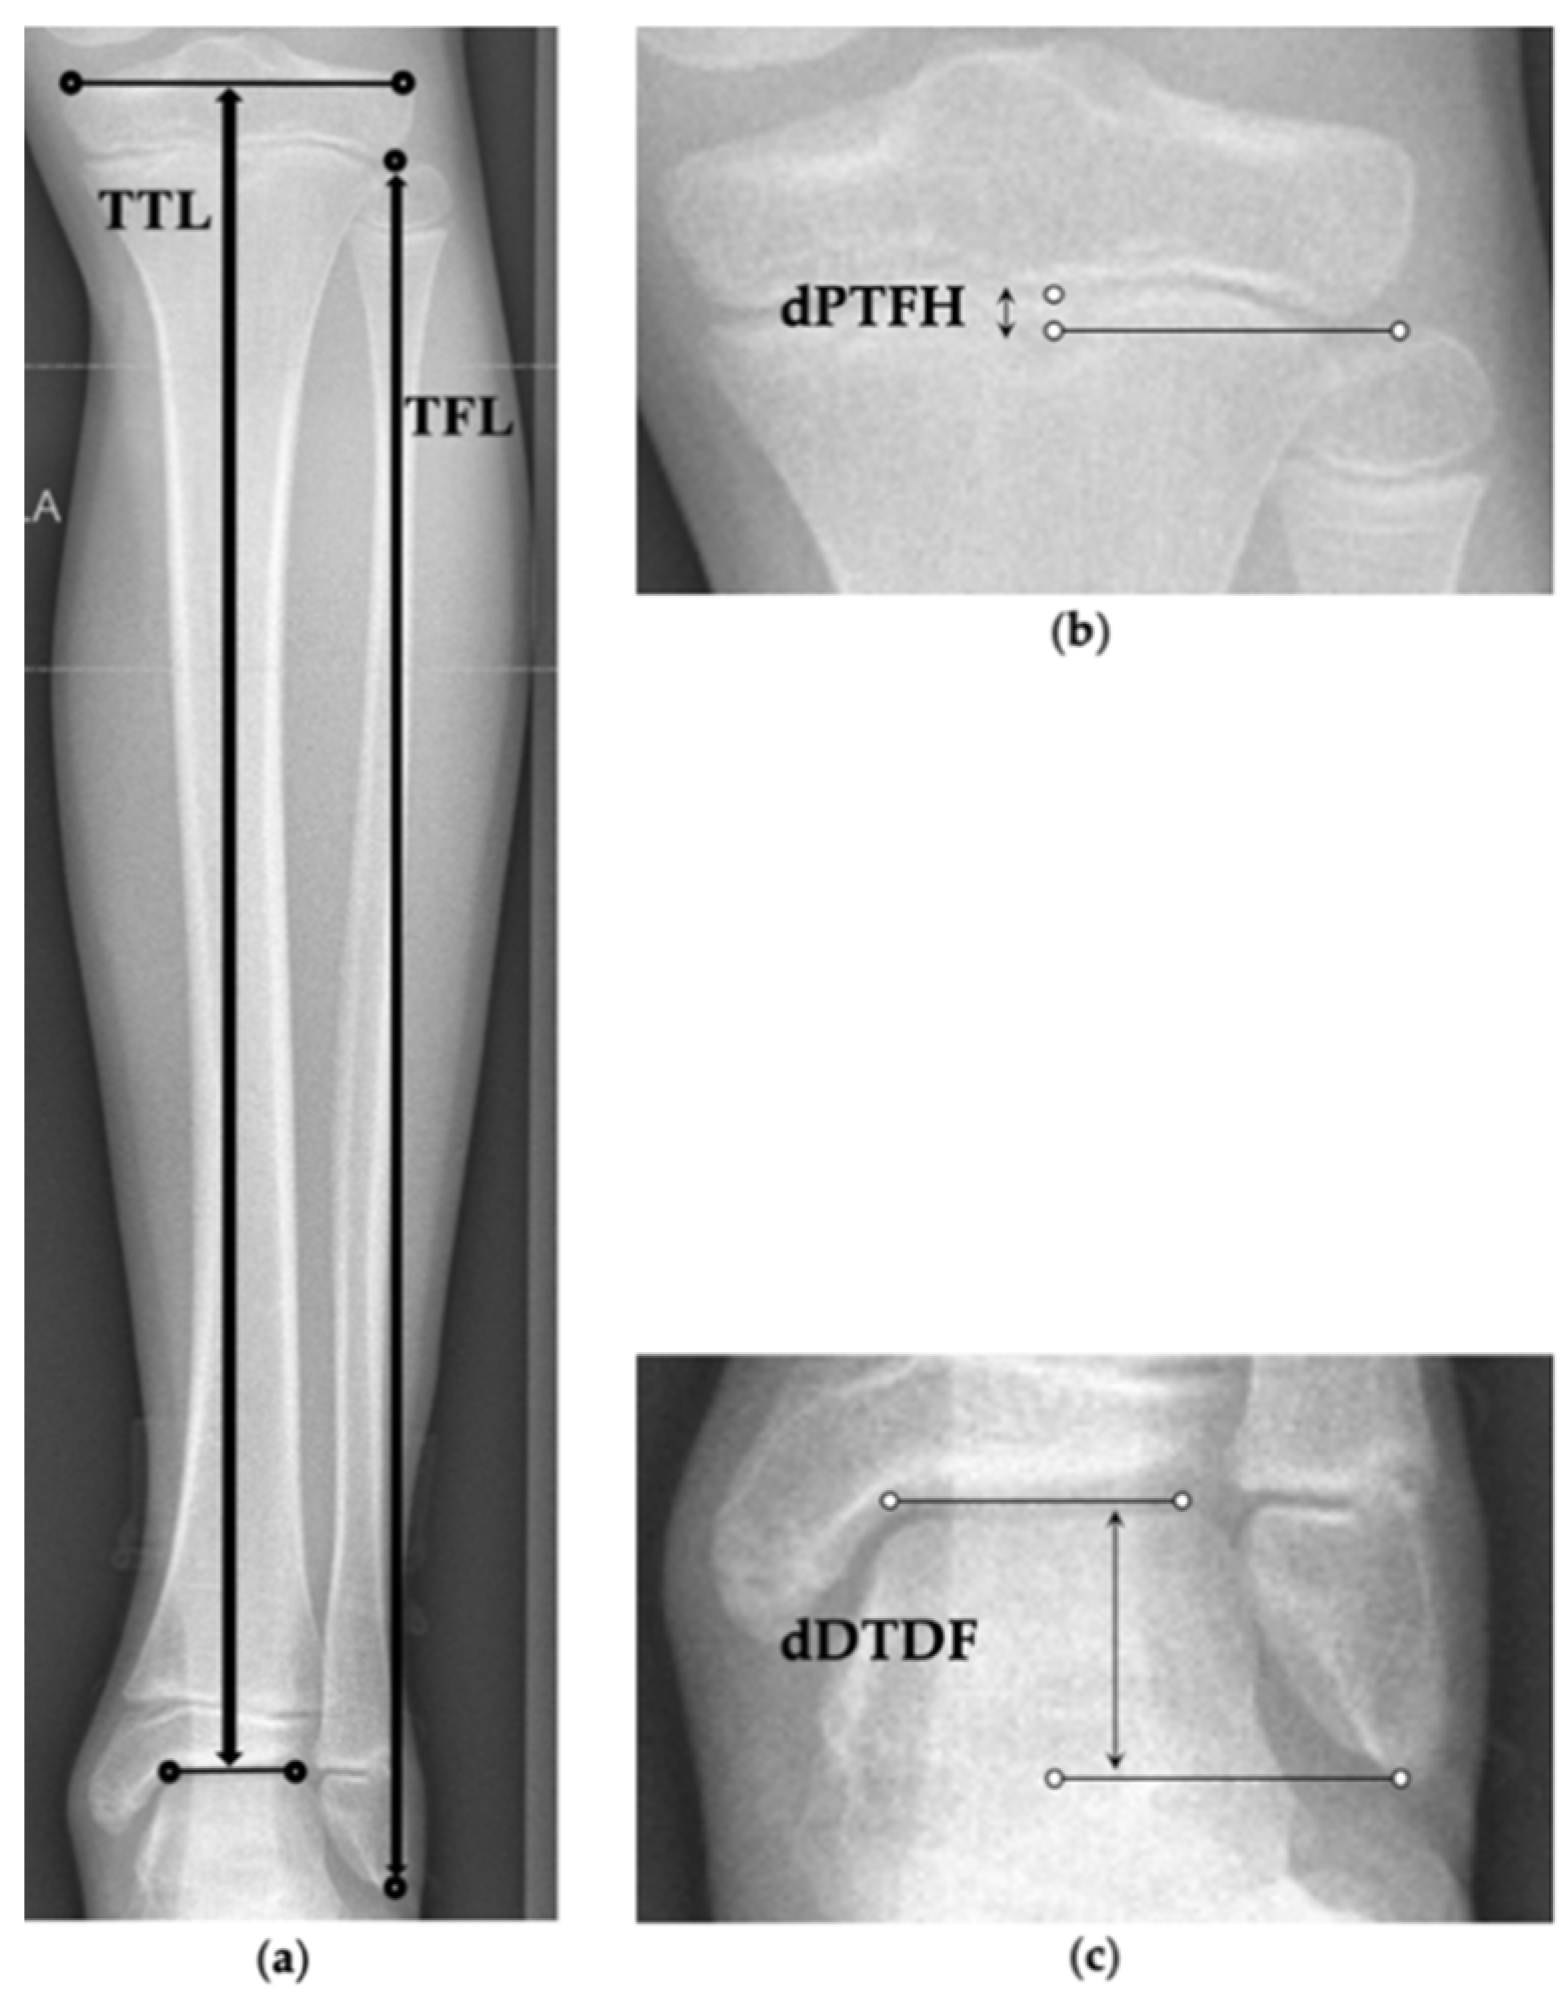

2.5. Radiographic Analysis

3.2. Radiographic Outcome Regarding Tibiofibular Relation